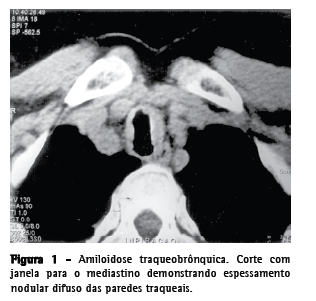

Traqueobroncomegalia

A traqueobroncomegalia, também chamada de síndrome de Mounier-Kuhn, se caracteriza por acentuada dilatação da traquéia e brônquios principais devido a uma atrofia ou ausência das fibras elásticas longitudinais e da musculatura lisa que formam suas paredes.(13,14) A principal alteração observada na fisiologia respiratória desses pacientes é o colapso total das vias aéreas durante a expiração.(2,14) Com o reflexo de tosse e mecanismo de defesa mucociliar prejudicados, as vias aéreas se encontram extremamente alargadas e enfraquecidas, o que causa retenção de muco, pneumonia recorrente e fibrose.(2,13,15) Desta forma, os sintomas são pouco específicos e relacionados às infecções recorrentes, incluindo expectoração excessiva, hemoptise e dispnéia.(2) A TC de tórax demonstra aumento do diâmetro das grandes vias aéreas (Figura 3). Observam-se ainda diminuição da espessura da parede traqueal, bronquiectasias e divertículos, que normalmente se originam da parede póstero-lateral.(2,13-15)

Papilomatose laringo-traqueo-brônquica

A papilomatose laringo-traqueo-brônquica é uma infecção das vias aéreas, causada pelo papilomavírus humano, potencialmente capaz de apresentar degeneração maligna.(2,3) A laringe é comumente envolvida, enquanto o acometimento traqueal é raro, ocorrendo em cerca de 5% dos pacientes com papilomatose laríngea.(2,3,16) Os papilomas podem ser únicos ou múltiplos.(3) O sintoma inicial mais comum é a rouquidão, causada pelo comprometimento das cordas vocais verdadeiras. Com a disseminação da doença, o paciente pode apresentar graus variáveis de obstrução das vias aéreas, com sibilos, atelectasias, pneumonias recorrentes e bronquiectasias. A hemoptise ocorre com freqüência, sendo a infecção comumente confundida com tuberculose ativa.(16) Os achados radiográficosincluemlesõespolipóides,pediculadas ou sésseis localizadas na traquéia e nos brônquiosfonte. Nódulos com distribuição centrolobular, que comumente escavam, localizados predominantemente nas metades basais e posteriores dos pulmões são vistos na TC quando há o acometimento distal das vias aéreas (Figura 4). No caso de haver infecções superimpostas, podem ser identificados nível líquido no interior das escavações, áreas de consolidações e atelectasias.(2,3,16,1)